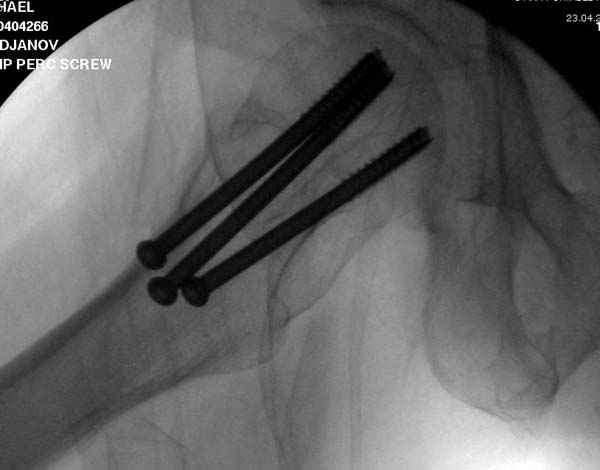

Наверное речь идет насчет parallel guide из набора. Применяем по возможности всегда, но,

как видно на снимке, не всегда получается

паралельно.

Такие несмещенные переломы обычно для молодых резидентов, и бывают технические неточности, но в этом случае посчитали фиксацию адекватной.

Соблюдая правила, многократными попытками можно

увеличить риск стрессового перелома латерального

кортекса.